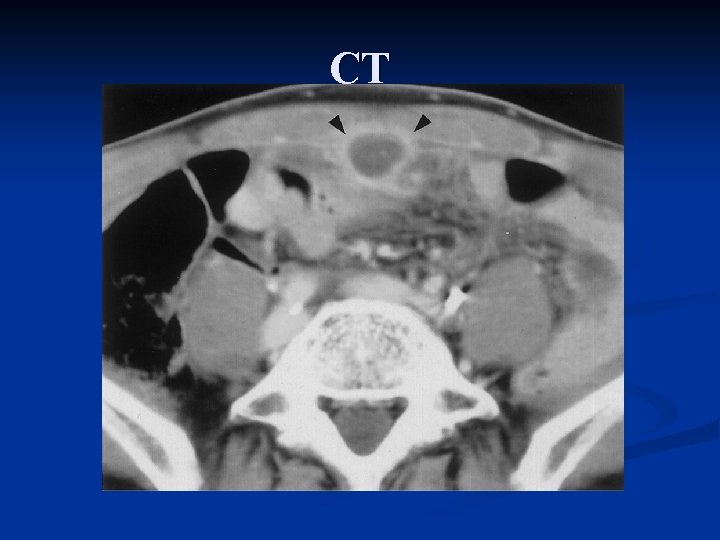

Urachal abnormalities • • failure of obliteration of urachus resulting complete or partial patency of urachus < 1/1000 live births inflammation or drainage from umbilicus US, CT, contrast studies, or injection of dye into tract can confirm diagnosis

CT